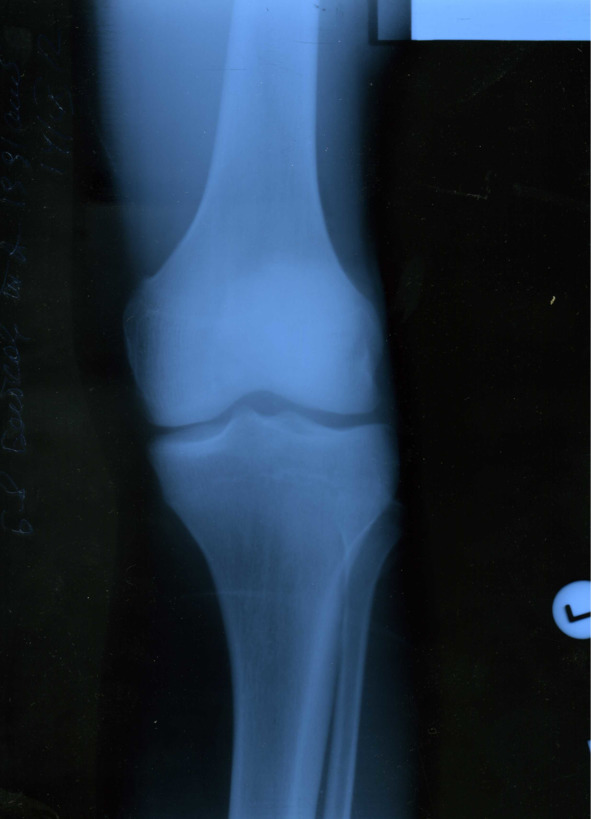

В сентябре 2012 года, когда уже оба сустава по кругу обострялись ни один раз, в очередной раз случилось обострение, и я все-таки решил обратиться к коллеге-хирургу за обследованием и профессиональной помощью. После общего осмотра было назначено рентген-обследование коленных суставов (все снимки представлены ниже).

Изменения малозаметны, но все же диагноз хронический остеоартроз подтвердил врач-рентгенолог, хирургом назначены обезболивающие средства и аппликации сустава димексидом.